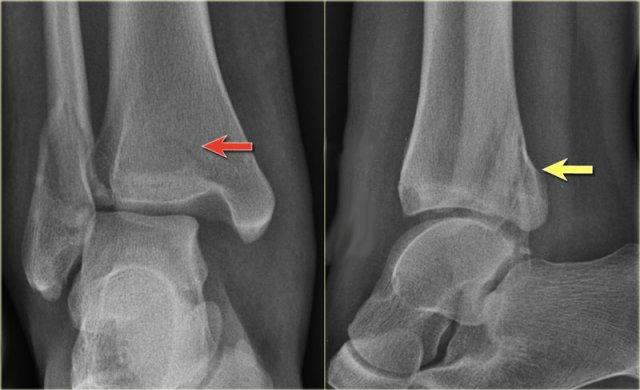

This can best be demonstrated by giving an example.

- Ấn tượng ban đầu

Các phim chụp X-quang cho thấy gãy mắt cá sau.

Nếu bạn chỉ mô tả đơn thuần là – gãy mắt cá sau – thì bạn đã bỏ sót vấn đề chính.

Đây có thể là gãy xương cổ chân không vững.

Gãy mắt cá sau đơn thuần là một phát hiện rất hiếm gặp.

- Nhìn vào hệ thống phân loại

Khi chúng ta xem xét sơ đồ, chúng ta sẽ nhận thấy rằng gãy mắt cá sau trong hầu hết các trường hợp là một phần của gãy Weber B hoặc Weber C.

Gãy xương thứ ba (tertius) thuộc Weber B giai đoạn 3

hoặc – do Weber C giai đoạn 4 (mũi tên).

Chúng ta cần xem lại phim để tìm các dấu hiệu bổ sung.

Vì bây giờ chúng ta đã biết cần tìm ở đâu, việc phát hiện các dấu hiệu bổ sung sẽ dễ dàng hơn.

- Tái khám

Trên phim chụp cổ chân không có dấu hiệu gãy xương chéo của mắt cá ngoài, do đó chúng ta có thể loại trừ gãy xương Weber B.

Vẫn còn khả năng gãy xương Weber C giai đoạn 4, tức là đứt hoặc bong gân phía trong, gãy xương mác cao và cuối cùng là gãy mắt cá sau.

Khi tái khám, bạn nhận thấy hình ảnh bong điểm bám tinh tế của mắt cá trong (mũi tên đỏ), đây là giai đoạn 1.

Cũng lưu ý tình trạng sưng nề phần mềm ở phía trong (mũi tên xanh)

Các phim X-quang bổ sung của chi dưới được chỉ định và cho thấy gãy xương mác cao, tức là Weber C giai đoạn 3, còn được gọi là gãy xương Maisonneuve.

Final report

Weber C fracture stage 4.

This is un unstable ankle injury that needs surgical repair.